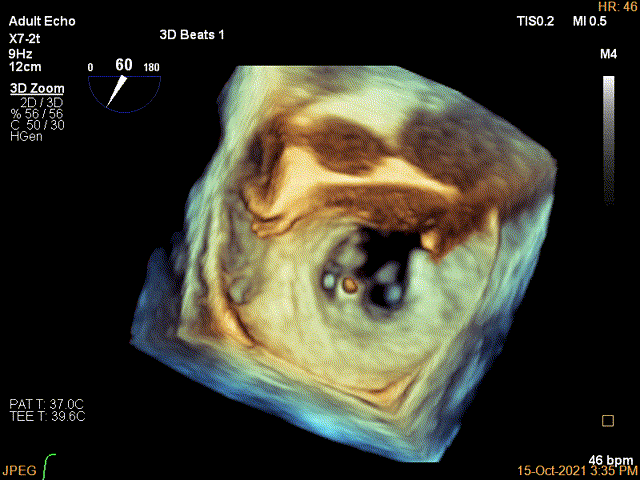

3D确认左房较大,穿刺点位近似于3点位

(2)该患者双房明显扩大,空间结构出现了扭转,在Bi-Plane平面LVOT view看不到左室流出道,因此术中通过3D zoom将主动脉瓣旋转到12点钟方向 ,穿刺位置最好为3点钟,自内交界区上方较合适,确定穿刺高度后,左心房3D成像确认。因此,对于这类患者结合3D视图找到最合适的房间隔穿刺点是成功的关键。